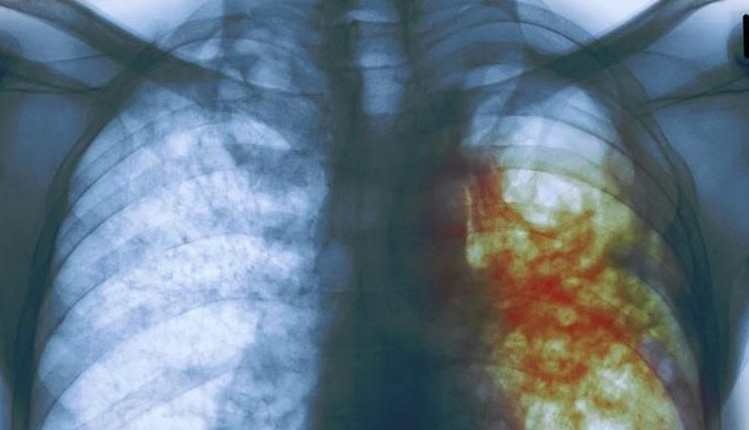

Radiografía de una persona con tuberculosis. (Foto Prensa Libre: Hemeroteca PL)